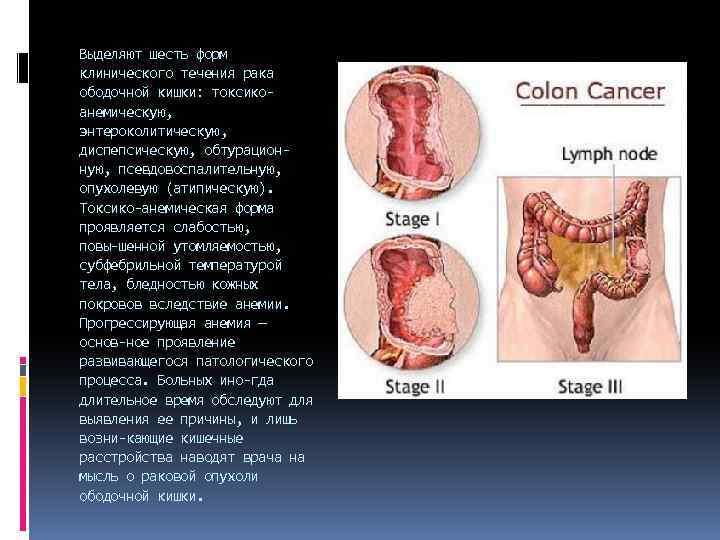

Выделяют шесть форм клинического течения рака ободочной кишки: токсико анемическую, энтероколитическую, диспепсическую, обтурацион ную, псевдовоспалительную, опухолевую (атипическую). Токсико анемическая форма проявляется слабостью, повы шенной утомляемостью, субфебрильной температурой тела, бледностью кожных покровов вследствие анемии. Прогрессирующая анемия — основ ное проявление развивающегося патологического процесса. Больных ино гда длительное время обследуют для выявления ее причины, и лишь возни кающие кишечные расстройства наводят врача на мысль о раковой опухоли ободочной кишки.